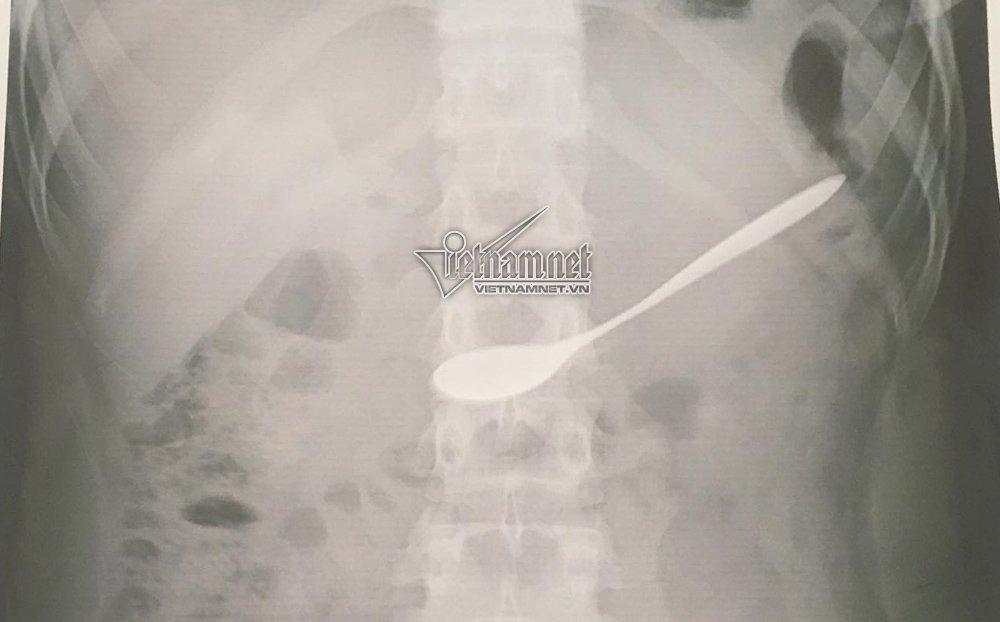

Phim x-quang cho thấy chiếc thìa nằm trong dạ dày

Tại đây, các bác sĩ đã chụp X-quang, xác định chiếc thìa nằm tại hang vị dạ bày của bệnh nhân.